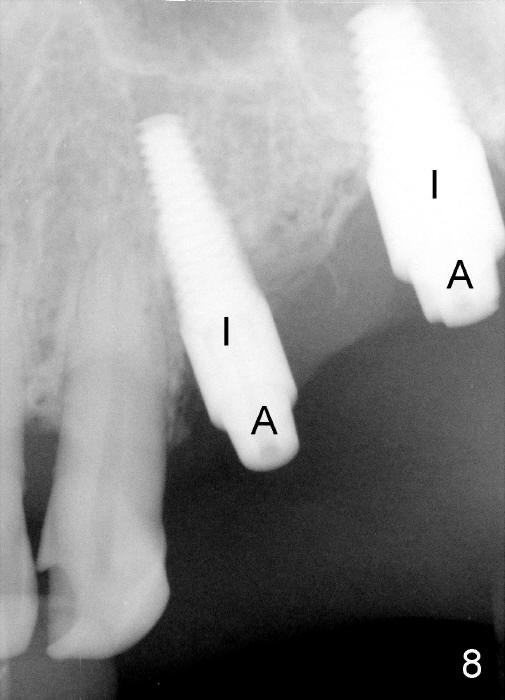

Initially the osteotomy is established with drill/reamers alternated with taps in the septum near the palatal socket. When a 4.5x14 mm tap (Fig.6 T; Fig.7: #14) is inserted, the sinus floor is perforated, but the sinus membrane is intact. When 7x14 mm tap is inserted, the sinus membrane is perforated in the buccal aspect of the osteotomy. The latter is repaired by placement of collagen dressing and then bone graft and membrane again (sandwich). The osteotomy is shifted to the palatal socket by using 5x14 and 6x14 mm taps. When the last tap is removed, the small area of the buccal aspect of the osteotomy is also found to be perforated, but the membrane is intact. When a 6x14 mm implant is placed (Fig.8), the coronal end is close to the middle of the socket (buccopalatally, due to angulation of the palatal socket).

Placement of immediate implant at the site of #12 is relatively easy. Adjustment is more or less mesiodistal. A 2 mm pilot drill (Fig.6 P) is found close to the root of the tooth #11 (red dashed line). The osteotomy is then moved distally (Fig.6 arrow). When 4.5x20 mm tap (Fig.7: #12) and 4.5x17 mm implant (Fig.8 I) are placed, there is distance from the root of the neighboring tooth. Insertion torque of the both implants is >60 Ncm. Abutments are placed (A in Fig.8) for immediate provisional.

Buccal to #14 implant/abutment is a large defect, which is filled with allograft and Osteogen and covered by collagen membrane (Fig.9 M). The defect at the site of #12 is mesiopalatal, which is repaired in the same fashion (Fig.10: M). The collagen membrane is in turn protected by the "overhang" (extension) of the immediate provisional bridge (Fig.11,12 *). Once the wounds heal (Fig.13, 9 days postop), the extension is trimmed (Fig.14).